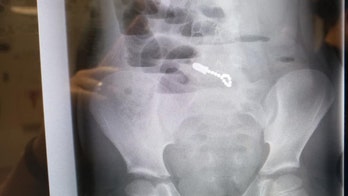

November 14, 2018 Utah boy accidentally swallows fidget magnets while hiding toy from brother, family says A Utah boy is recovering from his third surgery after he accidentally swallowed 14 magnets while hiding a fidget cube from his older brother in his mouth.